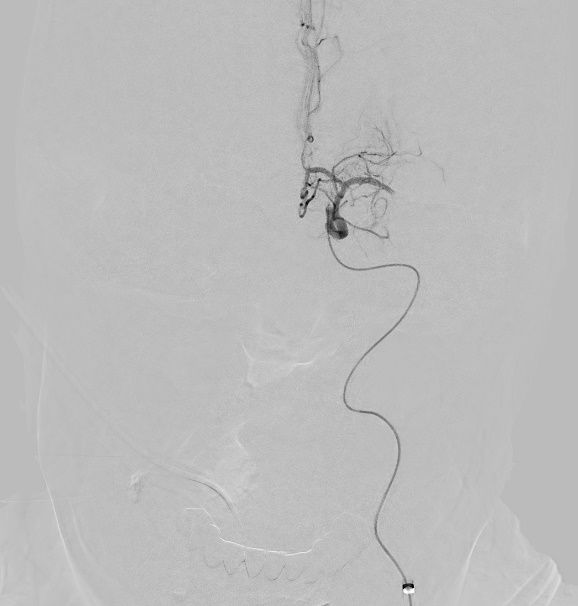

A microscopic photo illustrating carotid artery blockage

1- Carotid artery blockage in neck

a microscopic photo illustrating left middle cerebral artery clot

2- Left middle cerebral artery clot

a microscopic photo illustrating stent in carotid artery and clot removed from middle cerebral artery

3- Stent in carotid artery and clot removed from middle cerebral artery

Mechanical thrombectomy is the usual treatment when an ischemic stroke only involves one large brain-vessel blockage. It involves threading a catheter through the groin or wrist to reach the occluded vessel and remove the blood clot.

Treatment is more complex when a patient suffers a stroke with tandem occlusion. Doctors must decide between two endovascular options, treat the neck first or treat the brain first. Studies have shown benefits to both approaches:

• Neck first: For the antegrade approach, a balloon and stent are used to open the blocked carotid artery. Next, the blockage in the brain vessel is removed by threading a catheter through that freshly opened neck artery to the blood clot in the brain.

• Brain first: For the retrograde approach, the goal is to get the brain reoxygenated as quickly as possible to prevent further damage. A balloon is used to open the neck blockage just enough to get a catheter through to the brain blood clot. Once the brain vessel blockage is cleared, the doctor can back track to the ballooned neck artery and open it more firmly with additional ballooning and/or a stent.